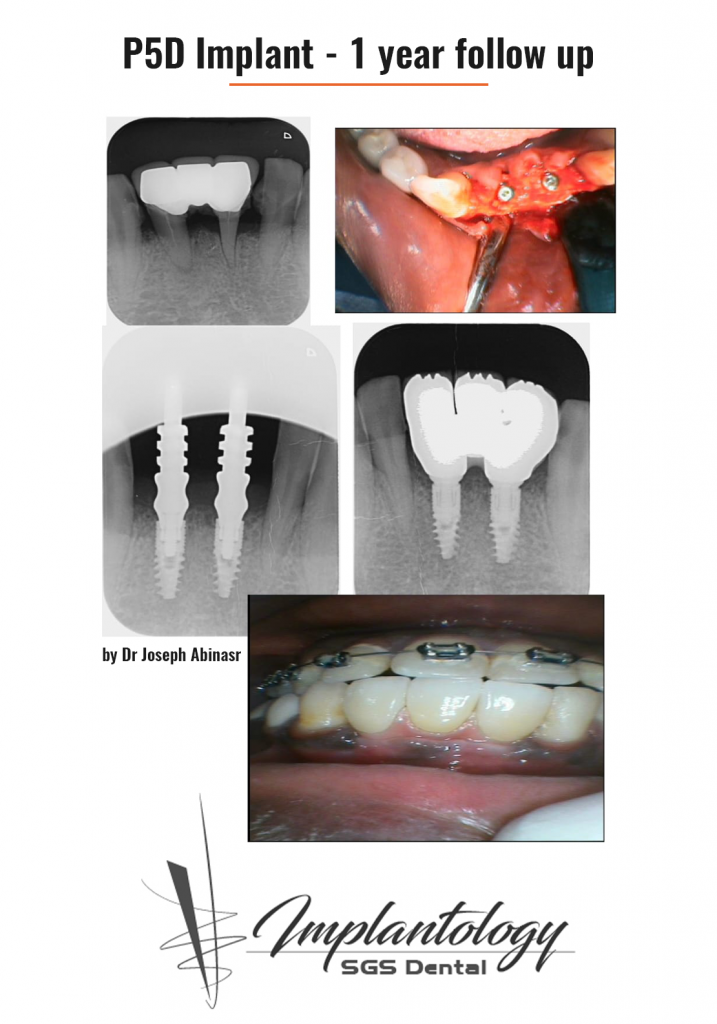

P5D имплантат – один год после установки

Клинические кейсы